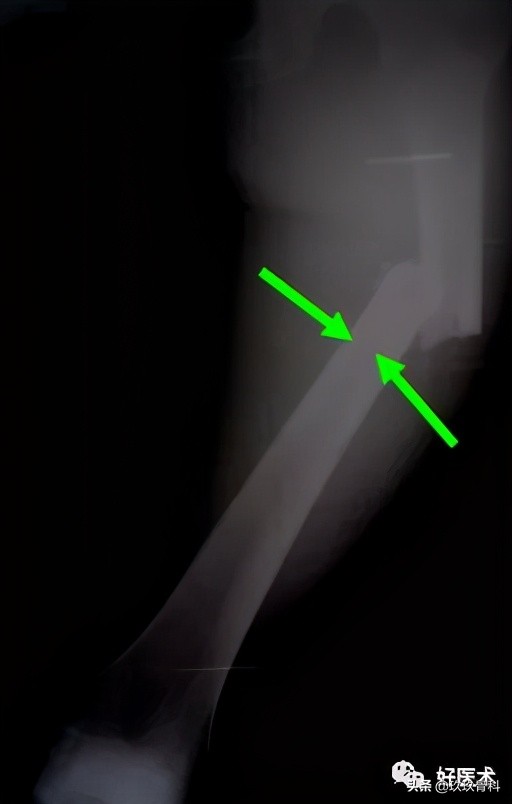

2)胫骨骨折复位

- 手法复位

- 绝大部分在皮下容易摸到

- 稳定骨折-中段或远段A型和B型骨折

- 斜形骨折-矫枉过正

- 髓内钉→复位工具

3)辅助复位措施

- 点状复位钳:

--胫骨

--经皮或伤口用

- 大牵开器(支架):

--延迟复位

--肢体短缩

- 临时Schanz螺钉

--股骨、胫骨

--尽可能靠近骨折线

--近端骨折单皮质使用

--用带T型手柄的万用卡盘便于操作

- Poller钉

--干骺端骨折

(纠正力线、稳定复位、复位操作)

--胫骨或股骨远端斜形骨折

(剪式应力→压力)

--位置差的髓内钉二次手术时钉进入旧髓腔通道

--进针点不好,近端骨折位线差

(螺钉放在与内植物可能移位的垂直方向)

(七)延迟&不愈合手术的复位技术

1.延迟手术可能遇到的问题

- 轴向畸形(短缩、成角和或移位)

- 肉芽组织长入

- 早期骨痂

- 骨折断端硬化,髓腔封闭

- 骨质疏松

2.术中可能出现的问题

- 扩髓器和髓内钉偏斜→髓内钉穿出皮质

- 成角畸形→牵开器

- 断端错位→Poller钉 钢板固定

3.防止力线异常的方法

- 近段-进针点正确

- 远端-髓内钉位于髓腔中心

- 近端或远端干骺端骨折